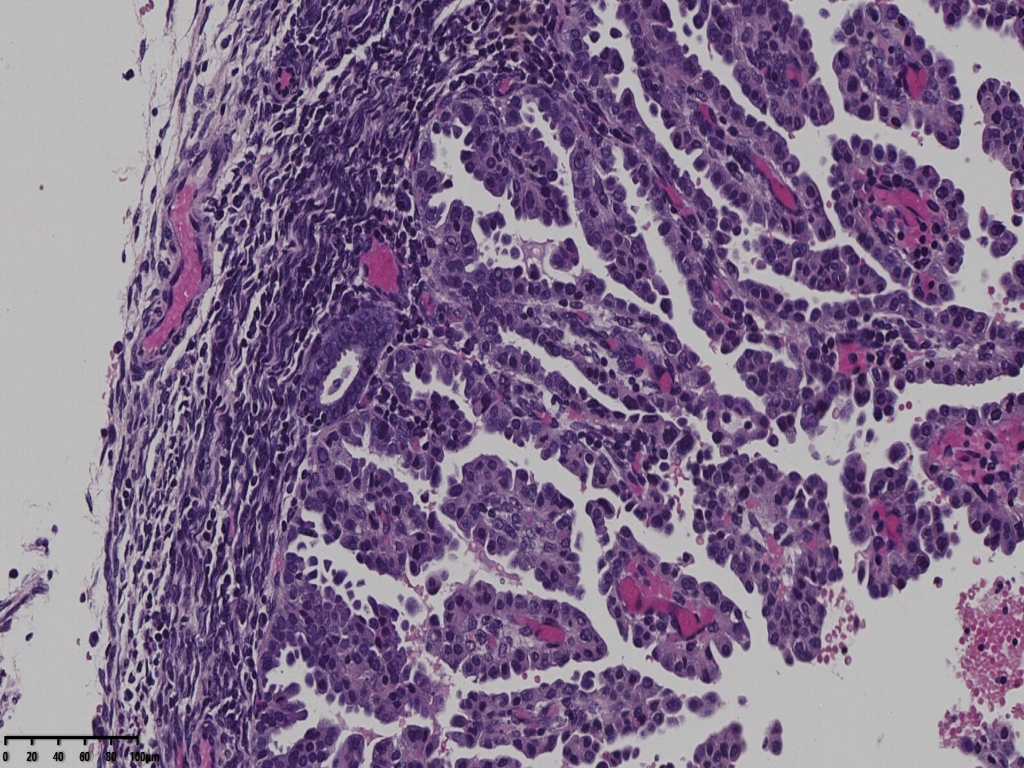

局部分区域腺体偏实性,细胞核大,周围胞浆空亮,会诊为子宫透明细胞癌,是不是就依据这一点?

但是其余部位内膜可见微乳头结构。